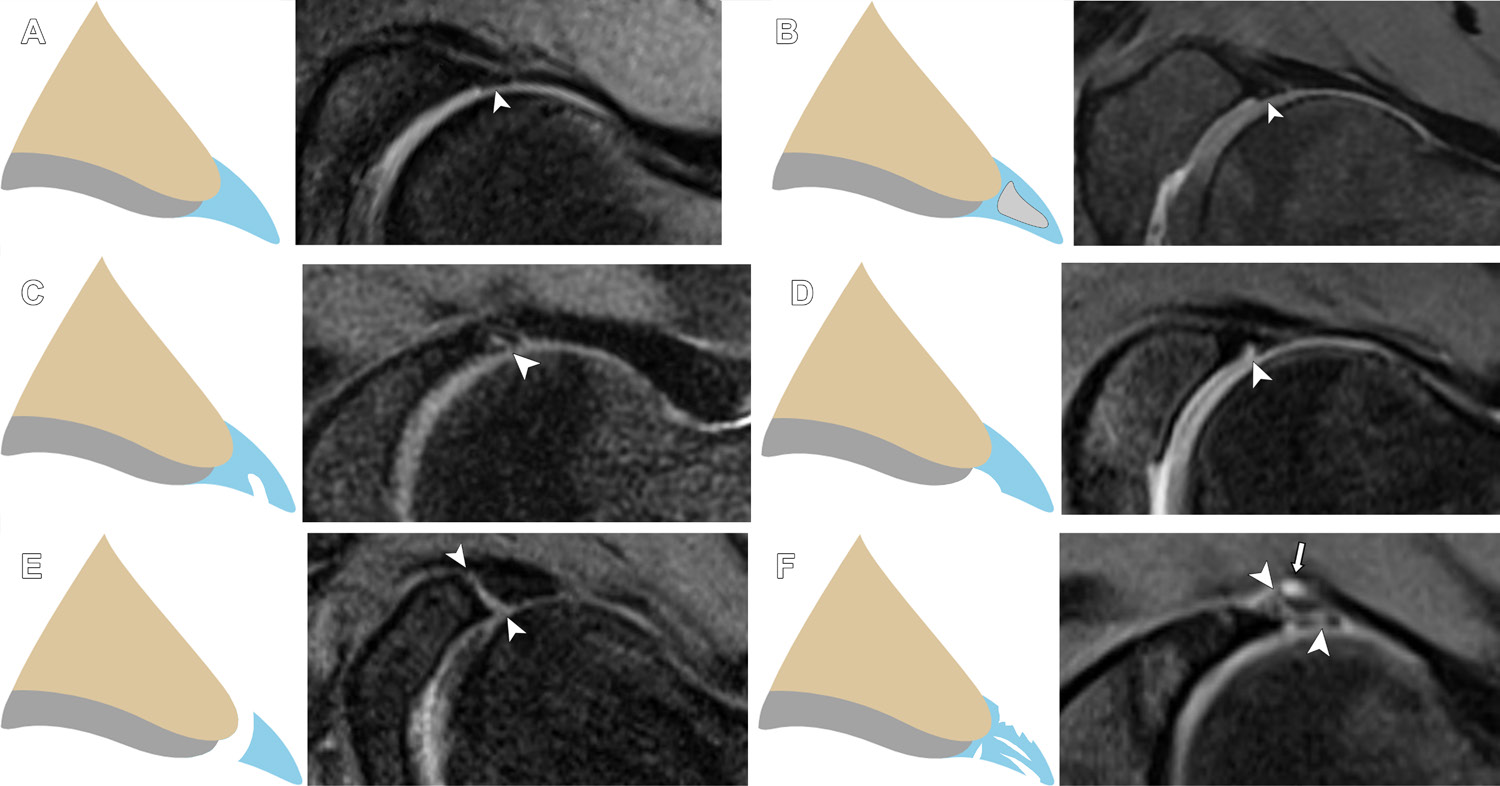

髋关节的关节囊盂唇复合体:解剖、疾病、术前与术后MRI特征(2024)HipCapsulolabralComplex:Anatomy,Disease,MRIFeatures,andPostoperativeAppearance FloresDV,FosterR,SampaioML,RakhraKS.HipCapsulolabralComplex:Anatomy,Disease,MRIFeatures,andPostoperativeAppearance[J].Radiographics,2024,44(2):e230144. 转载文章的原链接1:https://pubmed.ncbi.nlm.nih.gov/38300815/ 转载文章的原链接2:https://pubs.rsna.org/doi/10.1148/rg.230144?url_ver=Z39.88-2003&rfr_id=ori:rid:crossref.org&rfr_dat=cr_pub%20%200pubmed AbstractThehipisauniquelyconstrainedjointwithcriticalstaticstabilityprovidedbythelabrum,capsuleandcapsularligaments,andligamentumteres.Thelabrumisafibrocartilaginousstructurealongtheacetabularrimthatencirclesmostofthefemoralhead.Labraltearsarelocalizedbasedontheclock-facemethod,whichdeterminestheextentofthetearwhileprovidingconsistentterminologyforreporting.Normallabralvariantscanmimiclabraldiseaseandcanbedifferentiatedbyassessmentofthicknessorwidth,shape,borders,location,andassociatedabnormalities.TheLageandCzernyclassificationsystemsarecurrentlythemostwell-knownarthroscopicandimagingsystems,respectively.Femoroacetabularimpingementisariskfactorfordevelopmentoflabraltearsandisclassifiedaccordingtobonedysmorphismsofthefemur("cam")oracetabulum("pincer")orcombinationsofboth(mixed).Thecapsuleconsistsoflongitudinalfibersreinforcedbyligaments(iliofemoral,pubofemoral,ischiofemoral)andcircularfibers.Capsularinjuriesoccursecondarytohipdislocationoriatrogenicallyaftercapsulotomy.Capsularrepairimproveshipstabilityattheexpenseofcapsularovertighteningandinadvertentchondralinjury.Theligamentumteresissituatedbetweentheacetabularnotchandthefoveaofthefemoralhead.Initiallyconsideredtobeinconsequential,recentstudieshaverecognizeditsroleinhiprotationalstability.Existingclassificationsystemsofligamentumterestearsaccountforinjurymechanism,arthroscopicfindings,andtreatmentoptions.Injuriestothelabrum,capsule,andligamentumteresareimplicatedinsymptomsofhipinstability.Theauthorsdiscussthelabrum,capsule,andligamentumteres,highlightingtheiranatomy,pathologicconditions,MRIfeatures,andpostoperativeappearance. 图1 Abbreviations:FAI=femoroacetabularimpingement,ILFL=iliofemoralligament,ISFL=ischiofemoralligament,MRA=MRarthrography,PDFS=protondensity–weightedfat-suppressed,PFL=pubofemoralligament,T1FS=T1-weightedfat-suppressed TEACHINGPOINTS„ Byconvention,labraltearsarelocalizedbasedontheclock-facemethod,where3o’clockisanterior(demarcatingtheanteriorsuperiorandanteriorinferiorquadrants),6o’clockisthetransverseligament,and12o’clockisthesuperiorapexoftheacetabulum.Thiswasshowntobeanaccuratemethodthatmatchesthearthroscopist’slocalizationandimpressionoftheextentoflabraltears,therebyprovidingastandardizedmethodofreporting.„ Incontradistinctiontolabraltears,whichareirregularandextendintothelabralsubstance,themarginsofthelabrumattheinterfacewithasulcuswillbesmooth.Otherfeaturesthatfavorasulcusoverateararelessthanone-halflabralwidthfluidsignalintensitybetweenthebaseofthelabrumandtheacetabularrim;linearshape;absenceofregionalparalabral,cartilage,orosseousabnormalities;andposteriorinferiorquadrantlocation.„ Incontrasttothenativelabrum,increasedsignalintensityintheoperatedlabrumthatsurfacesisnotnecessarilyaretearandmayrepresentgranulationtissueorahealedtear.Increasedfluid-orgadolinium-intensitysignalwithinthelabrumthatsurfaces,extensionoflabralabnormalitybeyondthesutureanchorzoneorbeyondthemarginsoftheoriginaltear,paralabralcyst,andlabraldistortionaresignsofaretear.„ Capsularlesionsintheabsenceoftraumatichipdislocationmayberelatedtoopenorarthroscopiccapsulotomyorcapsulardehiscence.Intheabsenceofcapsularrepair,postoperativechangestotheadjacentstructures,capsularirregularity,edema,orafrankdefectmayindicatethesiteofarthroscopytrocarplacement.Capsulardehiscenceisapossiblecomplicationofcapsularrepair.ItisappreciatedatMRIasadisruptedordiscontinuouspseudocapsule,oftencharacterizedbyafluid-filledgapwithorwithoutassociatedpseudocapsularthickeningandhyperintensity.„ Iatrogenicinstabilityisararepostarthroscopycomplication.Osseousriskfactorsincludeexcessiveboneremovalduringacetabularrimresectionorfemoralosteoplasty.Largecapsulotomieswithoutcapsularrepairandnonhealingcapsulardefectsfrompreviousarthroscopyareexamplesofsoft-tissueriskfactors. IntroductionThehipisaball-and-socketjointconsistingofthecuplikeacetabulum,whichreceivesthesphericalfemoralhead.Itisauniquelyconstrainedjoint,inlargepartduetolarge-volumecoverageofthefemoralheadbytheacetabulum.Staticstabilityisfurtherprovidedbythreeimportantsoft-tissuestructures:thelabrum,capsuleandcapsuloligamentouscomplex,andligamentumteres(Fig1). Figure1.Graphicillustrationdepictsthecapsulolabralcomplexofthehip. Thelabrumandcapsulearecriticalcomponentsofthejoint’sstrongsuctionmechanism,maintainingtheintra-articularhydrostaticpressurenecessarytocontainthefluidwithinthecentralcompartment(1).Thecapsuleandcapsularligamentsallowafullrangeofmotionbutrestrictmovementsthatpredisposetosubluxationanddislocation.Theligamentumteresisasecondarystabilizerofthehip,supplementingthecapsularligamentsbyactingasa“sling”topreventsubluxationofthefemoralheadattheextremesofmotion.Thesize,variableform,andorientationofthesestabilizers,alongwithcloseappositionofthejoint’sarticularsurfaces,makeimagingevaluationchallenging.Furthermore,theadventofhiparthroscopyhasincreasedrecognitionofnumerouspathologicconditionsaffectingthesestructures,requiringcarefulscrutinybytheradiologist.Thisarticlediscussesthelabrum,capsule,andligamentumteres,emphasizingtheiranatomy,pathologicconditions,MRIfeatures,andpostoperativeappearance.Hipinstability,asourceofmuchcontroversyanddebate,isalsodiscussed,highlightingtheterminologyandclassification. ImagingConsiderationsConventionalradiographyremainsthefirstlineofimagingforinvestigationofallhipdisorders.Inthecontextofcapsulolabralstructures,itallowsevaluationofosseousdysmorphismsthatmaypredisposetolabraltearsorhipinstability,including“cam”and“pincer”femoroacetabularimpingement(FAI),hipdysplasia,andosteoarthritis.USisusefulinscreeningfortendondisease,muscletears,jointeffusion,andperiarticularfluidcollections.CT,withitscross-sectionalcapabilityandstrongdepictionofosseousmorphology,allowscharacterizationofhipdysplasiaandcamorpincerdeformitiesinmultiplanarandthree-dimensionalforms(FigS1).Inpatientswhoarecandidatesforjoint-preservationsurgery,italsoenablescalculationofimportantmetricssuchasacetabularandfemoralversion(2).MRIremainstheimagingtoolofchoicefordirectevaluationofthelabrum,capsularligaments,andligamentumteres(3).Optimizedprotocolsincludeadedicatedsurfacecoil,targetedfieldofview,thinsectionthickness,andhighin-planeresolutiontodepicttheanatomyanddiseaseofthesesmallstructures.Theadditionofthree-dimensionalacquisitionsthatuseisotropicvoxels(voxelswiththesamedimensionsinthex,y,andzplanes)enablesimagestobereconstructedinanyplane(4).Radialreconstructions,specifically,generateimagesorientedperpendiculartothecurvatureofthejoint,henceprovidingtruecrosssectionsofallquadrantsofthejoint.Theyareunhinderedbypartial-volumeeffects,optimizingdepictionofcartilageandthelabrum,whichisparticularlyimportantininvestigationofFAI(5).VisualizationofcapsulolabralstructuresisfurtherimprovedbycombiningMRIwithintra-articularcontrastmaterialorMRarthrography(MRA).Comparedwiththestandardofreferenceofarthroscopy,MRAexhibitsspecificity,sensitivity,andaccuracyof100%,92%–100%,and93%–96%,respectively,fordiagnosinglabraltears(6–8).Recentstudieshavedemonstratedthatconventionalornonarthrographic3-TMRImaybeadequateforevaluationofthelabrum(9–11).Astudyof38patientswithsuspectedFAIfoundaspecificityof50%butsensitivity,accuracy,positivepredictivevalue,andnegativepredictivevalueof98%–100%fornonarthrographicMRIwitharthroscopyasastandardofreference(9).Anotherinvestigationof68patientswithFAIalsofoundthatconventional3-TMRIisequivalentto1.5-TMRAfordetectinglabraltears(12).Arecentmeta-analysisfoundthatthesensitivityof3-TMRIwasclosetothatofMRA(pooledsensitivityof80%vs89%)anditsspecificitywashigherthanthatofMRA(pooledspecificityof77%vs69%)(11).Atourinstitution,conventional3-TMRIhasreplacedMRAastheworkhorseforinitialevaluationofhipinternalderangement.WereserveMRAforevaluatingapostoperativehiporyoungadultswithpersistentpainandnormalresultsof3-TMRI.MRAisthepreferredtechniquefordetectinghipcapsularandligamentumteresabnormalities(13,14).AninvestigationbyTomasevichetal(13)foundthatthesensitivityfordetectinghipcapsulardefectsafterhiparthroscopywassignificantlyhigherforMRAcomparedwithMRI(87.5%vs50%,respectively).MRAalsoshowssensitivity,specificity,positivepredictivevalue,negativepredictivevalue,andaccuracyfordetectionofligamentumterestearsof78%,97%,74%,97%,and95%,respectively(15).Theaxialobliqueplaneisparticularlyusefulfordifferentiatinggradesofligamentumteresinjuriesandimprovingspecificityfordifferentiationofpartialandcompletetears(14). AcetabularLabrumThelabrumistypicallytriangularincrosssectionandisfixedtotheacetabulumatitsbase(Fig2).Thebasehasdualattachment,spanningboththehyalinecartilage(chondrolabral)andtheacetabularbone(osseolabral).Atitschondralattachment,thelabrumstronglyadherestotheacetabularrimviaazoneofcalcifiedcartilageknownasthetidemark(16).Thechondrolabraljunctionhasavariabledegreeofblendingandevenoverlapofthelabrumwithacetabularhyalinecartilage.Thelabrumterminatesanteroinferiorlyandposteroinferiorly,whereitisbridgedbythetransverseacetabularligament.Exceptfortheregionclosesttothecapsule,thelabrumispoorlyvascularized,limitingitsabilitytohealoncetorn(17). Figure2.Normallabralanatomy.=paralabralrecess,arrowhead=osseolabraljunction,reddottedline=labralbase.(A)Graphicillustrationshowsnormallabralanatomy.(B)CoronalT1-weightedfat-suppressed(T1FS)MRarthrogramina39-year-oldhealthyasymptomaticvolunteershowsnormallabralanatomy.Yellowdottedline=tidemark. MRIoftheLabrumThenormallabrumtypicallyhasdiffuselowsignalintensitywithallMRIsequences.Intrasubstanceintermediateorhighsignalintensitycanbeseeninhealthyindividualsandmayrepresentmucoiddegeneration,fibrovascularbundles,ormagicangleartifact(3).Theanteriorsuperiorlabrumismostpronetosignalintensityvariations,includingglobular,linear,orcurvilinearshapes(18).Thelabrumisoftentriangular(66%–69%),althoughround(11%–16%)andflat(9%–13%)shapeshavebeenreported(18).Byconvention,labraltearsarelocalizedbasedontheclock-facemethod,where3o’clockisanterior(demarcatingtheanteriorsuperiorandanteriorinferiorquadrants),6o’clockisthetransverseligament,and12o’clockisthesuperiorapexoftheacetabulum(Fig3)(19).Thiswasshowntobeanaccuratemethodthatmatchesthearthroscopist’slocalizationandimpressionoftheextentoflabraltears,therebyprovidingastandardizedmethodofreporting(19). Figure3.Clock-facelocalizationoftheacetabularlabrum.Graphicillustration(A)andsagittalT1-weightedfat-suppressedMRimage(B)showclock-facelocalizationoftheacetabularlabrum.Thetransverseacetabularligament(highlightedinyellow)isassignedas6o’clock,withtheacetabulumdividedintoquadrants:3o’clockisanterior,9o’clockisposterior,and12o’clockissuperior(apexoftheacetabulum). LabralVariantsAsidefromvariationsinshapeandsignalintensity,groovesorspacesformedbythelabrumwitheithercartilage(sublabralsulci)orthecapsule(paralabralrecess)canbeconfusedwithalabraltear(18,20);theseareparticularlyconspicuouswiththedistentioneffectofMRA.Sublabralsulciarepresentinasmanyas25%ofpatientsandcanbefoundinallanatomicpositions,themostcommonbeingposteriorsuperior(48%)(Fig4)andanteriorsuperior(44%)(18).Incontradistinctionolabraltears,whichareirregularandextendintothelabralsubstance(18),themarginsofthelabrumattheinterfacewithasulcuswillbesmooth.Otherfeaturesthatfavorasulcusoverateararelessthanone-halflabralwidthfluidsignalintensitybetweenthebaseofthelabrumandtheacetabularrim;linearshape;absenceofregionalparalabral,cartilage,orosseousabnormalities;andposteriorinferiorquadrantlocation(20,21). Figure4.Sublabralsulcus.Axialobliqueprotondensity–weightedfat-suppressed(PDFS)MRimageina22-year-oldwomanwithhipdiscomfortafteranterosuperiorlabralrepairandosteochondroplastyandwithclinicalconcernforaretearshowsaposterosuperiorsublabralsulcus(arrowhead).Thereisalsoanadjacentparalabralrecess(arrow).Yellowdottedline=osseousdefectfrompriorosteochondroplasty.Resultsofarthroscopywerenegativeforalabralretear. Thejunctionofthetransverseligamentoverlappingwiththeacetabularlabrumcanalsoformanormalrecess(Fig5).Itismorecommonanteriorly(33%)andcanbeconfusedwithalabraltearoranteroinferiorlabral-ligamentousdetachment(18).Theparalabralrecessreferstothespacebetweenthecapsuleandthelabrum(Fig6)andcanbeconfusedwithaparalabralganglioncyst.Whilethecapsuleinsertsdirectlyatthebaseofthelabrumalongtheanteriorandposteriormarginsofthelabrum,itattachesseveralmillimetersabovethelabrumalongthesuperiormargin,therebymakingthisrecessmostobviousoncoronalsections(18). Figure5.Transverseligament–labraljunctionrecess.CoronalT1FSMRarthrogramina38-year-oldhealthyasymptomaticvolunteershowscontrastmaterial(arrowhead)atthejunctionbetweenthetransverseligamentandlabrum,consistentwithatransverseligament–labraljunctionrecess. Figure6.Paralabralrecess.CoronalT1FSMRarthrogramina26-year-oldfemaleasymptomaticvolunteershowscontrastmaterial(arrowhead)throughtheparalabralrecess,ananatomicspacecreatedbetweenthejointcapsuleandlabrum. LabralAbnormalitiesLabralabnormalitiesarereadilydemonstratedatMRI.Adegeneratedlabrummaymanifestwithincreasedsize,increasedintrasubstancesignalintensity,orsurfaceirregularity(22).Labraltearsoccureitherthroughitssubstanceorintheformofadetachmentofthebasefromtheadjacentacetabulum;upto90%ofcasesrepresentlabraldetachments(23).Substancetearmanifestswithincreasedsignalintensityorcontrastmaterialthroughthelabralsubstancesurfacingthearticularsurface,capsularsurface,orboth(22,23).Approximately28%oftearsmayexhibitsignalintensitylessthanthatofgadoliniumcontrastmaterialorfluid,possiblyduetoeithergranulationtissueorvolumeaveraging(24).Withlabraldetachments,increasedsignalintensityorcontrastmaterialundercutsthebaseofthelabrum,insinuatingbetweenthelabralbaseandacetabularrimeitherpartiallyorcompletely(25).Theevolutionoflabraldetachmenttypicallybeginsatthechondrolabraljunction.Intheearlieststages,theremaybeattritionoflabraltissueinthisregion,withfluidimbibitionbetweenthelabrumandhyalinecartilage—referredtoaschondrolabralseparation—orapartiallabraldetachment.Theseparationmayextendperipherallytowardthedirectionofthecapsule,resultinginadditionaldisruptionoftheosseolabraljunctionoracompletedetachmentofthelabrumfromtheacetabularrim(26).Thechondrolabraljunctionisofparticularinterestinthecontextofcam-typeimpingement,asitservesasthefirstsiteofderangementsecondarytoshearforceandcompressioninjuryofthehyalinecartilage(26).Thismayresultinchondraldelaminationleadingfromthechondrolabraljunctionandcoursinginward(26),theso-calledcarpetlesion(27).Classificationsystemsforlabraldiseaseexistinboththeorthopedicandradiologyliterature.TheLageclassificationisthemostwell-knownarthroscopicsystemandorganizeslabraltearsasflap,fibrillated,longitudinalperipheral,orunstable(28).Czernyetal(29)devisedanMRAclassificationforlabraldiseasebasedonlocation:withinthesubstance(types1and2)orattachment(type3)(Table,Fig7).Labraltearscanbesubstancetype(type2)ordetachmenttype(type3);theauthorsfoundthattypes2and3exhibitexcellentcorrelationwitharthroscopicfindings.Ontheotherhand,Blankenbakerandcolleagues(19)foundnocorrelationbetweentheCzernyandLageclassifications.TheauthorsalsorecommendeddescribingthelabralabnormalityratherthanattemptingtocorrelateitdirectlywiththeLageclassification(19). ClassificationofLabralInjuriesatMRASource.—Reference25. Figure7.RepresentativeanteriorsuperiorlabraltearsatMRAandtheirCzernyclassifications.(A)AxialobliqueT1FSMRarthrogramina20-year-oldwomanwithdailyandprogressivelefthippainshowsextensionofcontrastmaterialintothelabrum(arrowhead)withoutdetachment,consistentwithaCzernystageIIAlabraltear.(B)AxialobliqueT1FSMRarthrogramina40-year-oldwomanwithrecalcitranthipandgroinpainshowsimbibitionofcontrastmaterialintothedeformedlabrum(arrowhead),consistentwithaCzernystageIIBlabraltear.(C)AxialobliqueT1FSMRarthrogramina33-year-oldwomanwithclinicalsuspicionforlabraltearshowscontrastmaterial–filledexpansionofthelabrum(arrowhead)withdetachmentattheosseolabraljunction(arrow),consistentwithaCzernystageIIIBlabraltear. Atourinstitution,labraldiseaseisusuallyimagedusingconventional3-TMRI.Followingthisprotocolandincorporatingrecommendationsbypreviousauthors(19),weusethefollowingterminologyfordescribingcommonlabralpathologicconditions:(a)degeneration=increasedintra-substancesignalintensitywithoutsurfacing,(b)substancetear=increasedintrasubstancesignalintensityextendingtothecapsularorarticularsurfaceofthelabrum,(c)partialdetachmenttear=partial-widthincreasedsignalintensityextendingbetweenthebaseofthelabrumandacetabularrimatthechondrolabralorosseolabraljunction,(d)completedetachmenttear=increasedsignalintensitybetweenthelabrumandacetabularrimextendingacrossthefullwidthofthelabralbase,and(e)complextear=multidirectionalormultipleincreased-signal-intensitytearlines,extendingtoboththedeeparticularandcapsularsurfaces(Fig8)(22). Figure8.Normalandabnormalanteriorsuperiorlabrum.(A)Graphicillustration(left)andaxialobliquePDFSMRimage(right)ina27-year-oldasymptomaticvolunteershowanormallabrumwithhomogeneouslowsignalintensity(arrowhead),preservedtriangularshape,andsmoothborders.(B)Graphicillustration(left)andaxialobliquePDFSMRimage(right)ina36-year-oldwomanwithhippainandclinicalconcernforlabraltearshowasmallareaofincreasedsignalintensity(arrowhead)withinthelabralsubstancenotreachingasurface,consistentwithlabraldegeneration.(C)Graphicillustration(left)andaxialobliquePDFSMRimage(right)ina43-year-oldwomanwithsymptomsofimpinge-mentshowfocallinearincreasedsignalintensity(arrowhead)withinthelabralsubstancebreachingthearticularsurface,consistentwithasubstancetear.(D)Graphicillustration(left)andaxialobliquePDFSMRimage(right)ina37-year-oldwomanwithpersistenthippain,querylabraltear,showpartial-widthincreasedsignalintensity(arrowhead)atthechondrolabraljunctionnotextendingpastthechondrolabraljunction,consistentwithchondrolabralseparationorpartiallabraldetachment.(E)Graphicillustration(left)andaxialobliquePDFSMRimage(right)ina78-year-oldwomanwithsymptomsofimpingementshowincreasedsignalintensity(arrowheads)extendingcompletelyfromthechondrolabraljunctiontothelabralbase,consistentwithcompletelabraldetachment.(F)Graphicillustration(left)andaxialobliquePDFSMRimage(right)ina51-year-oldwomanwithlefthippainworsewithrunningshowmultipleincreased-signal-intensitylines(arrowheads)extendingtobothdeeparticularandcapsularsurfaces,consistentwithacomplextear.Asmallparalabralcyst(arrow)atthecapsularsurfaceisalsopresent. Chroniclabraltearanddegenerationcanresultinlabralossification,whichmayexacerbateimpingementsymptoms.AtMRI,ossificationappearsasasmallfocusofsignalintensitysimilartothatofbonemarrow(26)—althoughitmayevenbeoccult—andisthereforebestevaluatedonradiographsorT1-weightedimages(Fig9).Thepresenceofossificationshouldbereported,asitmayleadtoamoredifficultrepair,makinglabraldébridementtheoptimalapproach(30). Figure9.Completelabraldetachmentwithossificationina32-year-oldmalecyclist.CoronalT1-weighted(A)andPDFS(B)MRimagesshowasmallfocusofossification(arrowinA)adjacenttothesuperolateralacetabulumwithmarrow-equivalentsignalintensity,consistentwithossification.Thereisafluid-filledcleft(arrowheadinB)extendingcompletelyfromthechondrolabraljunctiontothelabralbase,consistentwithcompletelabraldetachment. Contrarytotearsinitsglenoidcounterpart,acetabularlabraltearsmostcommonlyoccurintheanteriorsuperiorquadrant(23).Tearsoftheposteriorsuperiorquadrant(Fig10)areusuallyseeninyoungerpatients,indysplastichips,orafteraposteriorhipdislocation(19).Posteriorinferiorlabraltears(Fig11)arerareandshouldnotbeconfusedwiththerelativelycommonnormalgrooveorsulcus,whichiswelldepictedatMRA(31). Figure10.Posteriorsuperiorlabraltearina46-year-oldwomanwithlockingandhippain.SagittalPDFSMRimageshowsincreasedsignalintensitywithintheposteriorsuperiorlabrum,consistentwithalabraltear,withanadjacentsmallparalabralcyst(arrow). Figure11.Posteriorinferiorlabraltearina48-year-oldmanwithdeeplefthippainradiatingtothegroin.Axialoblique(A)andsagittal(B)PDFSMRimagesshowafluid-filledcleft(arrowheadinA)withanadjacentcyst(arrowinB),consistentwithalabraltearwithasmallparalabralcyst. Aparalabralcystcanarisewhensynovialfluidleaksthroughalabraltearcleftandintotheperiarticularsoft-tissuespaceandbecomesencapsulated.Itaidsinrecognitionofalabraltearandisoftenlocatedintheanteriorsuperiorquadrant(32).ParalabralcystsusuallyhavelowtointermediatesignalintensityonT1-weightedimagesandhighsignalintensityonT2-weightedimages,althoughsignalintensitycanvary(33).Owingtotheirthickgelatinouscontent,theymaynotalwaysfillwithgadoliniumcontrastmaterialatMRA(22).Avastmajorityofparalabralcystsareaccompaniedbyfull-thicknesslabraldetachmenttears(94%)(Fig12);thelackofalabralteartherebyraisesthepossibilityofanotherdiagnosis,suchassynovialcyst,focalsynovitis,tumor,orpsoasbursalfluid(33). Figure12.Anteriorsuperiorlabraltearwithaparalabralcystina68-year-oldwomanwithrighthippainandanincidentalsoft-tissuemassatpreviousCT.SagittalPDFSMRimageshowsaprominentfluid-filledcleft(arrowhead)intheanteriorsuperiorlabrumwithanadjacentlargecysticmass(arrows),consistentwithacompletelabraldetachmenttearwithaparalabralcyst. FemoroacetabularImpingementFAIisawell-recognizedriskfactorinthedevelopmentandevolutionoflabraltearsandhiposteoarthritis.Itisassociatedwithanatomicalterationsthatimpairinteractionsbetweenthefemurandacetabulumduringmotionofthehipjoint,predisposingthelabrumtotearsandarticularcartilagetoprematuredegeneration.Itisclassifiedaccordingtobonedysmorphismascam(femoralside),pincer(acetabularside),oracombinationofbothtypes(mixed).Cammorphologyischaracterizedbyexcessboneorcartilageatthefemoralhead-neckjunction,diminishingthefemoralheadsphericityandhead-neckoffset.Pincermorphologypredisposestoimpingementduetoovercoverageofthefemoralheadbytheacetabulum.Itmaybefocal,asseenwithacetabularretroversion,orglobal,asisseenwithcoxaprofundaandacetabularprotrusio.Incammorphology,labralandchondraldisordersoccurpreferentiallyintheanteriorsuperiorquadrantofthejoint.Withpincermorphology,abutmentoftheanterioracetabularrimontothefemoralneckresultsinfocalimpactionandtearingoftheanteriorsuperiorlabrum,whicheventuallyextendsposteriorlyandultimatelycircumferentially(34). TreatmentandPostoperativeAppearanceLabraldiseasecanbemanagedwithconservativeorsurgicaloptions.Ingeneral,increasedlabralsubstancesignalintensitythatdoesnotbreachasurface(degenerativesignalintensity)isconservativelymanaged.Whiletheintraoperativeappearanceofthelabrum(ie,labralquality)(35)isthemostimportantoverallfactoraffectingsurgicaldecisionmaking,asurveybyHerickhoffandSafran(36)showedthatsurgeonsconsiderMRIorMRAfindingstobethemostimportantpreoperativefactor.Indicationstorepairatornacetabularlabrumandtypesoftreatmentarehighlyvariableamonghiparthroscopicsurgeons(35,36).Therearethreeformsoflabralsurgery:débridement,refixationorrepair,andreconstruction.Labraldebridementinvolvestrimmingoffrayedandunhealthytissue,potentiallyleavingviabletissuewithgoodhealingcapacity(37,38).Labralrefixationorrepairinvolvesreattachmenttotheacetabularrimusingsutureanchors(38).Substancetearsaretreatedwithdébridementwithorwithoutrepair,whilepartialorcompletedetachmentsaremanagedwithrepair.Incaseswherethereisinsufficientlabraltissuethatprecludesadequaterepair,suchasinasmallordiminutive(hypotrophic)labrumlessthan3mmwide,complextear,ormaceratedlabrum,labrumreconstructionusinganauto-orallograftcanbeperformed(38).Anormalpostoperativelabrumshouldbefirmlyaffixedtotheacetabularrimandremainintactoverthesutureanchorzone(39).Itistypicallyshorteranddiminutivebutshouldremainsmooth(40).Thesuturesthemselvesshouldbepositionedclosetotheacetabularrimbutshouldnotpenetratethesubchondralboneorthearticularcartilage(41,42).Kimandcolleagues(43)foundobliterationoftheparalabralrecessin94%–100%ofhiparthroscopyprocedures;thismaybeanormalpostoperativefindingrelatedtoadhesionsorscarring(Fig13)(43),althoughthisfindingmaybeworthreportinginthepresenceofsymptoms(43).Incontrasttothenativelabrum,increasedsignalintensityintheoperatedlabrumthatsurfacesisnotnecessarilyaretearandmayrepresentgranulationtissueorahealedtear(Fig14)(22,40).Increasedfluid-orgadolinium-intensitysignalwithinthelabrumthatsurfaces,extensionoflabralabnormalitybeyondthesutureanchorzoneorbeyondthemarginsoftheoriginaltear,paralabralcyst,andlabraldistortionaresignsofaretear(Fig15)(40). Figure13.Postoperativeobliterationoftheparalabralrecessina40-year-oldwomanwithpersistentlimitedrangeofmotionafterlabralrepair.CoronalPDFSMRimagesbefore(A)and1yearafter(B)arthroscopiclabralrepairshowobliterationofthepreviouslyintactsuperiorparalabralrecess(arrowinA)andreplacementwithill-definedintermediate-signal-intensitytissue(arrowheadsinB),mostinkeepingwithfibrosisorscarring. Figure14.Normalpostoperativelabrumina48-year-oldwomanimagedforassessmentofaretear.SequentialPDFSMRimagesatamoreanterior(A)andposterior(B)levelshowsignalintensitywithinthelabrumthatsurfacestobothcapsularandarticularsides(arrowheadsinA),whichmaybeworrisomeforaretearinanativelabrum.Thesutureanchorsareplacedclosetotheacetabularrim(arrowsinB)butdonotbreachthesubchondralboneorarticularcartilage.Arthroscopydemonstratedanintactposteroperativelabrum. Figure15.Labralretearina36-year-oldwoman.CoronalT1FSMRarthrogramshowsdistortionoftheanteriorsuperiorlabrumwithimbibitionofcontrastmaterial(arrowheads),consistentwithalabralretear. TheosseousdysmorphismresponsibleforFAIisusuallytreatedalongwiththelabraltear.Thetwomostimportantfactorstoconsiderinchoosingthetechniquearevisualizationoftheentirelesiontoachieveathoroughcorrectionorrepairwhilemaintainingthebiomechanicalfunctionofthejoint(44).Osteochondroplastyisthemostpopularmethodformanagingcamdeformitiesandinvolvescorrectiveresectionofthecammorphologyusingahigh-speedburr(Fig16)(44).AtMRI,theosteochondroplastybedappearsasasmoothdefectofvariablesizeatthefemoralhead-neckjunction(45). Figure16.Labralrepairwithsutureanchorina39-year-oldwomanwithlabraltear.(A)Intraoperativeimagebeforeresectionshowsaprominentfemoralhead-neckjunction(yellowdottedline),consistentwithcamdeformity.(B)Intraoperativeimageafterthecamhasbeenresectedshowsbonyconcavityofthefemoralhead-neckjunction(yellowdottedline),consistentwithpostexcisionchanges. Pincerlesionsaremanagedbyalabraltakedownandacetabularrimresectionfollowedbyreattachmentofthelabrumtotheacetabulumwithsutures(45).Theresectedportionappearsasadefectortruncationoftheacetabularrimwithorwithoutsuturesfromlabralsurgery(Fig17).Theappearanceoflabralprocedures,osteochondroplasty,andacetabularresectiondefectsmaybesubtle,attimesevenmimickingtheirnormalpreoperativecounterparts,necessitatingcarefulcomparisonwithpreprocedureimagesandoperativenoteswhenavailable. Figure17.Acetabularrimresectionandlabralrepairwithoutcapsularrepairina36-year-oldmanwithmixed-typeleftFAI.(A)PreoperativeaxialobliquePDFSMRimageshowsanintactanteriorsuperiorlabrumattachingtoanormalanteriorsuperioracetabulum(arrows).(B)PostoperativeaxialobliquePDFSMRimageshowsbonytruncationoftheanteriorsuperioracetabulum(arrows)andanadjacentfluid-filleddefectintheanteriorsuperiorcapsule(yellowdottedline)representingthearthroscopyportal.Alabralsutureisalsoshown(arrowheads). CapsuleandCapsularLigamentsoftheHipThehipcapsuleisacriticalstaticstabilizerofthehipandcontainsbothlongitudinalandcircularfibers(Fig18)(46).Thelongitudinalfibersarereinforcedbythreeligaments:iliofem-oral(ILFL),pubofemoral(PFL),andischiofemoral(ISFL).TheILFLorligamentofBigelowisthestrongestofthethree(46),limitingexternalrotationinflexionandbothinternalandexternalrotationinextension.Itconsistsofsuperiorandinferiorbandsthatextendfromthelowerpartoftheanteroinferioriliacspineandiliacmarginoftheacetabulumtotheintertrochantericline,formingareverse-Yconfiguration(46). Figure18.Graphicillustrationsshowtheosseousfootprints(A)andcourse(B)ofthecapsularfibersandligaments.Lightblue=superiorbandoftheiliofemoralligament(ILFL),pink=inferiorbandoftheILFL,green=ischiofemoralligament(ISFL),yellow=pubofemoralligament(PFL),orange=capsularfibers,whitebandinB=zonaorbicularis. ThePFLstabilizesthejointmostnotablyduringabduction.Itcoursesanteriorlyfromtheobturatorcrestandsuperiorpubicramustothefemoralneckadjacenttothelessertrochanter,blendingwiththeinferiorfibersoftheILFL.TheISFLcontributestojointstabilityduringextension.Itcoursesfromtheischialaspectoftheacetabularrimtothegreatertrochantericbaseposteriortothehip.ThezonaorbicularismakesupthecircularfibersandrepresentsacircumferentialcapsularthickeningattachingsuperiorlytothefemuratthebaseofthegreatertrochanterbeforeconvergingwiththesuperiorbandoftheISFL(46).Itensheathstheposteriorcircumferenceofthefemoralnecklikeaslingandformsthedistalfreeborderoftheposteriorportionofthearticularcapsule.Whileconventionallythoughttobeinconsequentialtojointfunctionandbiomechanics,recentstudieshavepostulateditsrolesinrestrainingjointdistraction(47)andcirculatingsynovialfluidbetweenthecentralandperipheralcompartments(46). MRIoftheCapsularLigamentsAtMRI,thecapsularstructureshavehomogeneouslylowsignalintensitywithallsequences.TheILFLbandsandISFLarebestidentifiedintheaxialandaxialobliqueplanes(Fig19).CoronalsectionsattheanteriorcapsuledepicttheILFL,whilesagittalsectionsdemonstratethePFL(Fig20)(48).ThezonaorbicularisisdepictedatbothMRIandMRA;intra-articulargadoliniumcontrastmaterialenhancesvisualizationoftheligamentanditssynovialfolds(49).Althoughoftendescribedasformingacollararoundthefemoralneck,itappearsasafullcircleinonly20%ofcases(49). Figure19.NormalMRIoftheILFLina26-year-oldmaleasymptomaticvolunteer.(A)AxialobliqueT1-weightedMRarthrogramatamoresuperiorlevelshowsthesuperiorbandoftheILFLinsertingontothesuperioraspectoftheintertrochantericline(arrowhead).Medially,theinferiorbandoftheILFL(thickstraightarrow)isseenasadistinctthickeningontheanteriorcapsule.TheISFLappearsasathickeningoftheposteriorcapsule(curvedarrows).Thezonaorbicularis(thinstraightarrow)isafocalprominencethatformsthedistalfreeborderoftheposteriorcapsule.(B)AxialobliqueT1-weightedMRarthrogramatamoreinferiorlevelshowstheinferiorbandoftheILFL(arrow)insertingontotheinferioraspectoftheintertrochantericline(arrowhead). Figure20.NormalMRIofthePFLina26-year-oldmaleasymptomaticvolunteer.SagittalT1FSMRarthrogramshowsanintactPFL(arrows).Theiliopsoastendonisseenintheanterioraspectofthejoint(arrowheads). Capsuleandcapsularligamentinjuriesusuallyfollowdefinitivehipdislocationsafterhigh-energycontactsportinjuriesorimpactionofthekneeagainstacardashboardwiththehipflexed(50).Thedirectionisfrequentlyposterior,wheretheheadofthefemurliesposteriortotheacetabulumandtheinjuredlowerextremityexhibitsshortening,medial(internal)rotation,flexion,andadduction(51).Onanteroposteriorradiographs,anteriorandposteriordislocationsmayappearsimilar.However,inaposteriordislocation,thefemoralheadisusuallylocatedposterior,superior,andlateraltotheacetabulum(FigS2).ThepreciseroleofMRIintreatmentalgorithmsforacutehipdislocationisnotclearlydefined,butitmaybeusefulinearlyrecognitionofsoft-tissueinjuries(Fig21)(52)anddetectionofintra-articulardamagesuchaschondralinjury,labraltear,ormissedintra-articularbody(53).Theimagingtriadofposterioracetabularlipfracture,ILFLdisruption,andhemarthrosiswasfoundtobepathognomonicofposteriorhipdislocationinacaseseriesofeightfootballplayers(54). Figure21.HipdislocationatMRI.AxialT1FSMRarthrogramina23-year-oldwoman3daysafterareportedposteriorhipdislocationshowsaprominentdefectintheISFL(arrowheads)consistentwithacompletetear,withextravasationofcontrastmaterialintothesofttissues(arrows). Anteriordislocationisfarlesscommon,occurringinlessthan8%oftraumatichipdislocations(52).Themechanismofinjuryisforcedhipabductionandexternalrotation;thefemoralheaddislocatesanteroinferiorlywhenthehipisflexedandanterosuperiorlywhenthehipisextended(52).Thetransverseligament,ligamentumteres,posteriorcapsule,andPFLmaybeinjuredinanteriorinferiordislocations(52).Dataonanteriorsuperiordislocationsarelimited,althoughinjuriestotheligamentumteres,ILFL,andsuperiorcapsulehavebeenreported(52). PostoperativeAppearanceCapsularrepairortighteningprocedureshaveyettogainuniversalacceptanceamonghipsurgeons,eventhoughavastmajorityofhigh-volumearthroscopistsrecommendthemforcapsularredundancyorlaxityorafterarthroscopy(55).Theseproceduresimprovehipstabilityanddecreasetheriskofpostoperativehipdislocationattheexpenseofiatrogenicfemoralheadchondraldamage,capsuleovertightening,andhipinfectionduetolongerexposuretime.Capsularrepairorplicationusessuturestoclosethecapsular“barearea”atthesiteofpriorarthroscopy.Itisrecommendedforcapsularredundancy,symptomaticcapsularlaxity,orgeneralizedligamentouslaxityduetoanunderlyingconnectivetissuedisorderorafterarthroscopy(56).AtMRI,therepairedcapsuleisusuallysignificantlythickerthroughtheILFLatthesiteofroutinecapsulotomyandclosurecomparedwiththecontralateralnonoperativehip(57).Othercapsulartighteningproceduresarethermalcapsulorrhaphyandcapsularreconstruction(50,56).Capsularlesionsintheabsenceoftraumatichipdislocationmayberelatedtoopenorarthroscopiccapsulotomyorcapsulardehiscence.Intheabsenceofcapsularrepair,postoperativechangestotheadjacentstructures,capsularirregularity,edema,orafrankdefectmayindicatethesiteofarthroscopytrocarplacement(Fig22).Capsulardehiscenceisapossiblecomplicationofcapsularrepair.ItisappreciatedatMRIasadisruptedordiscontinuouspseudocapsule,oftencharacterizedbyafluid-filledgapwithorwithoutassociatedpseudocapsularthickeningandhyperintensity(58).Spontaneoushealingofthecapsulecanbeseenasearlyas6weeks,dependingonthearthroscopicapproach(Fig23)(59). Figure22.Postarthroscopycapsuledefectina41-year-oldwomanwhounderwentrecentlabralrepairwithoutcapsularrepair2weeksearlier.CoronalT1FSMRarthrogramshowsawell-demarcatedcontrastmaterial–filleddefectoftheILFL(arrowhead)withsurroundingsusceptibilityartifacts,consistentwithapostarthroscopycapsuledefect Figure23.Capsularhealingina46-year-oldmanwithpersistentimpingementsymptomsaftersurgery.(A)PostoperativePDFSMRimage2weeksaftercapsulectomyandosteochondroplastyshowsanewlyexcisedfemoralhead-neckjunction(arrow)withoverlyingill-definedsoft-tissueedema(arrowheads),consistentwithcapsulectomychanges.(B)PostoperativePDFSMRimage5.5monthsaftertheprocedureshowsintervalresolutionoftheedemaandfillinginofthecapsule(arrowheads),consistentwithcapsularhealing. LigamentumTeresTheligamentumteresisatubularligamentsituatedbetweentheperipheralinferioracetabularnotchandthefoveaofthefemoralhead.Itarisesfromthetransverseacetabularligamentalongtheinferiormarginoftheacetabulumandattachestotheperiosteumofthefoveabytwobands:ischialandpubic.Awarenessandinterestintheligamentumtereshaveincreasedwiththeexpansionofhiparthroscopy.Initiallyconsideredaninconsequentialvestigialstructure,recentstudieshaverecognizeditsroleinfemoralheadvascularity,proprioception,nociception,androtationalstabilityofthehip(14).Martinandcolleagues(60)describeditsroleinhipstabilityusingaball-and-stringmodel(Fig24). Figure24.Graphicillustrationsdemonstratethemechanismofhipstabilityprovidedbytheligamentumteres,accordingtotheballand-stringmodel.(A)Asthehipjointisabducted,theligamentumtereswrapsunderthefemoralheadwhilepullingitintotheacetabulum,limitinginferiorsubluxation.(B)Asthehipjointisexternallyrotated,theligamentumtereswrapsaroundthefemoralheadwhilepullingitintotheacetabulum,limitinganteriorsubluxation. MRIoftheLigamentumTeresLigamentumteresinjuriesareassociatedwithhipdislocation,flexion-adductionstress(ie,fallonipsilateralkneewiththehipflexed),orabruptexternalrotationofthehipsuchasintwisting(14).Variousclassificationsystemshavebeenproposed(61).GrayandVillar(62)firstclassifiedinjuriesbasedoninjurymechanismaswellasarthroscopicfindings.TheDombclassificationwasdevelopedtoquantifythedegreeofligamentruptureintype2lesionsorpartialtears(63).PorthosSalasandO’Donnell(64)proposedathirdclassificationtofurtherdelineatethecauseofthetearandincorporatetreatmentoptions.Finally,O’DonnellandArora(65)accountedforligamentouslaxityinadditiontotheligament’sappearance.AtMRI,theligamentappearsasasmooth,predominantlyhomogeneous,andlow-signal-intensitystructurewithallpulsesequences.Itisbestdepictedonaxialandcoronalimages,appearingasabilobedslightlystriatedligamentcomprisedofonetothreebundles(Fig25)(14,66).Ithasanaverageoveralllengthof28mmandmeasuresapproximately3–4mminthickness,graduallytaperingfromproximaltodistal(66).Slightlyincreasedsignalintensitynearitscurvedattachmenttothefoveacapitisfemorisonshortertimetoecho(TE)–basedimagesmaybeattributabletothe“magicangle”artifact(14). Figure25.NormalMRIoftheligamentteresintwopatients.(A)CoronalT1FSMRarthrogramina24-year-oldfemaleasymptomaticvolunteershowsanormalsinglebundleoftheligamentumterescoursingfromthefoveacapitis(arrowhead)tothetransverseacetabularligament(arrow).(B)CoronalT1FSMRarthrogramina30-year-oldfemaleasymptomaticvolunteershowsanormaldoublebundleoftheligamentumterescoursingfromthefoveacapitis(arrowhead)tothetransverseacetabularligament(arrow). Partialandcompletetearsaremostcommoninthefoveacapitis;thoroughinspectionofthisregionisthereforeimportant(14).WhileMRAhasbeenshowntobeaccurateindiagnosingligamentumterestears,literatureontheaccuracyofconventionalMRIissparse.AnintactligamentandapartiallytornligamentcanhavesimilarimagingfindingsatMRA,makingdiagnosisofpartialligamentumterestearsdifficult(66).Highsignalintensitywithinthesubstanceofthefibersandperipheralirregularityaresuggestiveofapartialtear(Fig26)(66).Acompletetearmanifestswithfull-thicknessfiberdiscontinuityandligamentlaxity. Figure26.Partialtearoftheligamentumteresina29-year-oldfemalesprinterwith4weeksofgroinpain.CoronalPDFSMRimageshowsfocaldiscontinuityofthesuperiorandmedialfibers(arrowhead)oftheligamentumteres,consistentwithapartialtear. AnondisplacedfracturefragmentmayaccompanyeitherapartialorcompletetearbutmaybeoverlookedatMRI,requiringcarefulevaluationofmarrowsignalintensityonprotondensity–weightedfat-suppressed(PDFS)orT2-weightedimages(14).ConventionalCTorCTarthrographymaybemoreoptimalforevaluatingfragmentscomparedwithMRIorMRA(Fig27).Achronicallytornligamentiselongated,irregular,lax,orattenuatedwithfibersremainingcontiguous.Absenceofedemaintheacetabularfossa,synovitis,andjointeffusionallowdistinctionofchronicfromacutetears(Fig28)(14). Figure27.Acuteavulsionfractureoftheligamentumteresina22-year-oldmanafterlefthipdislocation.(A)CoronalPDFSMRimageshowsanacuteavulsionfractureofthefovealattachmentoftheligamentumteres(arrowhead)andassociatedmarrowedemaintheacetabulum(arrows).(B)CoronalCTimageshowsasmallavulsedfragment(arrowhead).Thereisalsoanundisplacedfractureoftheadjacentmedialwalloftheacetabulum(arrow). Figure28.Chronictearoftheligamentumteresina45-year-oldformerbasketballplayerwith6yearsofinguinalpainexacerbatedbysquatting.CoronalPDFSMRimageshowsmarkedthickeningoftheligamentumteresatthefoveacapitis(arrowheads)withpreservedfibercontiguity,consistentwithachronictear. TreatmentComparedwithtreatmentsforlabralandcapsuledisease,therearelimiteddataonmanagementofligamentumteresinjuries.Formostcases,conservativemanagementisadequate.Tearsarecurrentlytreatedarthroscopically(67),andindicationscontinuetoevolve.Currentindicationsarepain,instability,andmechanicalsymptomswithMRIfindingsofligamentthickening,partialorcompletetears,oravulsionfractureoftheligamentwithintra-articularosteochondralfragmentsandedemaintheacetabularfossa(14).Treatmentoptionsareshrinkage,débridement,andmostrecentlyreconstruction.Shrinkageanddébridementarereservedforpartialtearsafterfailedconservativemanagement.Fibroblasticresponsefromthermalshrinkageimprovesthebiomechanicalstrengthoftheremainingfibers,whiledébridementoffrayedandthestumpoftornfibersrelievesmechanicalsymptomsandpain(14).Reconstructionwithallografts,autografts,orsyntheticgraftsisindicatedforcompletetearsthatareconsideredreparable,causeinstability,orfailedpreviousdébridement(67). HipInstabilityHipinstabilityisabroadtermusedtodescribevariousabnormalitiesmanifestingwithdeep-seatedpainaroundthehip,groin,oringuinalregion.Thetermhasbeenusedinterchangeablywithjointhyperlaxityorhypermobilityandmicroinstability(68).Awarenessoftheentityhasincreasedrecently,althoughitsdiagnosisandevenitsexistencearestilldebated.Disordersofthecapsulolabralstructureshavebeenimplicatedinsymptomsofhipinstability.Anexhaustivediscussionisbeyondthescopeofthisarticle,butthissectionwillemphasizecurrentclassificationandterminology.Hipinstabilitymaybe(a)duetoasingleacuteepisodeoftrauma,(b)duetooveruseorrepetitivemicrotraumainayoungorathleticpatient,(c)iatrogenicinthesettingofpriorarthroscopyandcapsulotomy,(d)developmentaloranatomicsuchasinhipdysplasiaorconnectivetissuedisorders(ie,hyperlaxity),or(e)idiopathicormicroinstabilitywhentheclinicalpresentationisvagueorintheabsenceofthepreviouslymentionedcriteria(68).Traumaticinstabilitysecondarytoanacutedislocationeventmaybedistinguishedfromoveruseinstabilityonlywithareliableclinicalhistoryandphysicalexamination.Iatrogenicinstabilityisararepostarthroscopycomplication.Osseousriskfactorsincludeexcessiveboneremovalduringacetabularrimresectionorfemoralosteoplasty(FigS3).Largecapsulotomieswithoutcapsularrepairandnonhealingcapsulardefectsfrompreviousarthroscopyareexamplesofsoft-tissueriskfactors(56,69).O’Neilletal(70)describedagradingsystemforcapsularchangesatMRAinpatientswithsymptomaticpostsurgicalhipinstability.Thissystemincludesnormalcapsularappearanceandvolume,increasedcapsularredundancy(Fig29),focalcapsularrentorcapsularirregularity,andgrosscapsulardefect.Intheircohortof31patients,nocapsulesappearedcompletelynormalaftertheprocedure(70).Contrarytotraumatichipinstability,postarthroscopicinstabilityismostoftenanterior(theanteriorlateralcapsulebeingthemostcommonportalforarthroscopy)andoccurswithhipextensionandexternalrotation(71).DevelopmentaloranatomicinstabilityisseeninpatientswithdysplastichiporFAI,connectivetissuedisorders,orhypermobilitysyndromes(Ehlers-DanlosorMarfansyndrome).Thealteredbonearchitectureintheseconditionspredisposestoearlychondropathyandlabraltearsintheabsenceoftrauma,athleticactivity,orsurgery.Finally,idiopathicinstabilityormicroinstabilityreferstopainfulextraphysiologichipmotionwithoutovertsubluxationordislocation(42).Whilecausesofmicroinstabilitycanbethesameasoroverlapwiththoseofthetypesmentionedearlier,itisoftenseeninpatientswholackadefiniteunderlyingcause.Asaresult,diagnosisreliesonathoroughclinicalhistory,physicalexamination,andimagingevaluation.Currently,therearenopathognomonicimagingfeaturesofmicroinstability.Arecentsystematicreviewfoundthatintheappropriateclinicalcontext,hipdysplasia,anteriorlabraltears,andligamentumterestearsmaybesuggestiveofmicroinstability,althoughtheauthorsrecommendfurtherstudies(42).Capsularlaxityisimplicatedinmicroinstabilitybutisnotadiagnosisperse(72).Itisatermusedtodescribetheinabilityofthejointtodelivernormalresistancetoexternalforces(72).Theterminologyisoftenusedinbiomechanicalandclinicalstudies.althoughafewinvestigationssuggestimagingcorrelates.Aprospectivestudyof100consecutivepatientsshowedlowerhypermobilityscoresinsubjectswithacapsularthicknessofgreaterthanorequalto10mm(73).AnotherstudybyMagerkurthetal(74)concludedthatawidenedanteriorhipjointrecess(>5mm)andathinnedanteriorjointcapsule(<3mm)correlatewithintraoperativefindingsoflaxity. ConclusionThehipisauniquelyconstrainedjointwithcriticalstaticstabilityprovidedbythelabrum,capsuleandcapsularligaments,andligamentumteres.Understandingtheanatomy,patternsofinjury,MRIfeatures,treatment,andpostoperativeappearanceallowsprecisediagnosisandtimelymanagement.